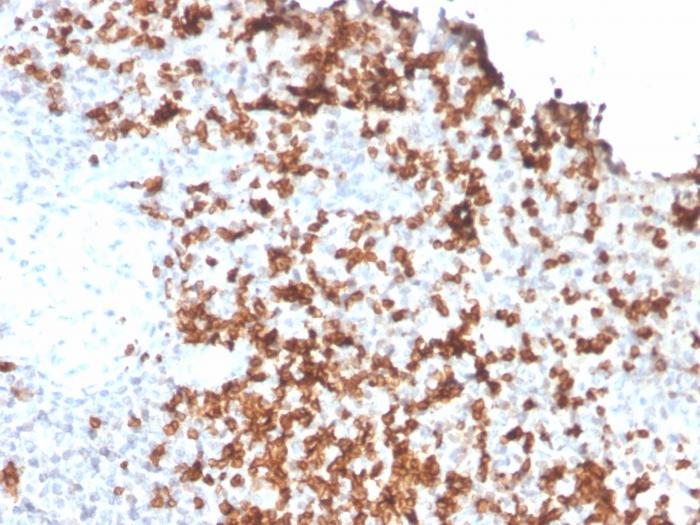

Granzyme B is a member of the granule serine protease family stored specifically in NK cells or cytotoxic T cells. Cytolytic T lymphocytes (CTL) and natural killer (NK) cells share the ability to recognize, bind, and lyse specific target cells. They are thought to protect their host by lysing cells bearing on their surface 'nonself' antigens, usually peptides or proteins resulting from infection by intracellular pathogens. Granzyme B is crucial for the rapid induction of target cell apoptosis by CTLs in the cell-mediated immune response. Granzyme B is useful as a marker in the identification of NK/T-cell lymphomas. High percentages of cytotoxic T-cells have been shown to be an unfavorable prognostic indicator in Hodgkin's Disease. Primary antibodies are available purified, or with a selection of fluorescent CF® Dyes and other labels. CF® Dyes offer exceptional brightness and photostability. Note: Conjugates of blue fluorescent dyes like CF®405S and CF®405M are not recommended for detecting low abundance targets, because blue dyes have lower fluorescence and can give higher non-specific background than other dye colors.

Positive Control

A431 cells. Human tonsil, spleen or Hodgkin' s Lymphoma tissue (IHC).

IHC, FFPE (verified)

IHC (FFPE) (verified)